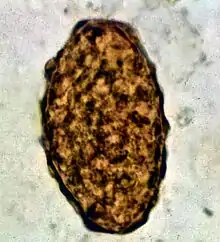

Ascaris lumbricoides is characterized by its great size. Males are 2–4 mm (0.08–0.2 in) in diameter and 15–31 cm (5.9–12 in) long. The male's posterior end is curved ventrally and has a bluntly pointed tail. Females are 3–6 mm (0.1–0.2 in) wide and 20–49 cm (7.9–19 in) long. The vulva is located in the anterior end and accounts for about one-third of its body length. Uteri may contain up to 27 million eggs at a time, with 200,000 being laid per day. Fertilized eggs are oval to round in shape and are 45–75 μm (0.0018–0.0030 in) long and 35–50 μm (0.0014–0.0020 in) wide with a thick outer shell. Unfertilized eggs measure 88–94 μm (0.0035–0.0037 in) long and 44 μm (0.0017 in) wide.[8]